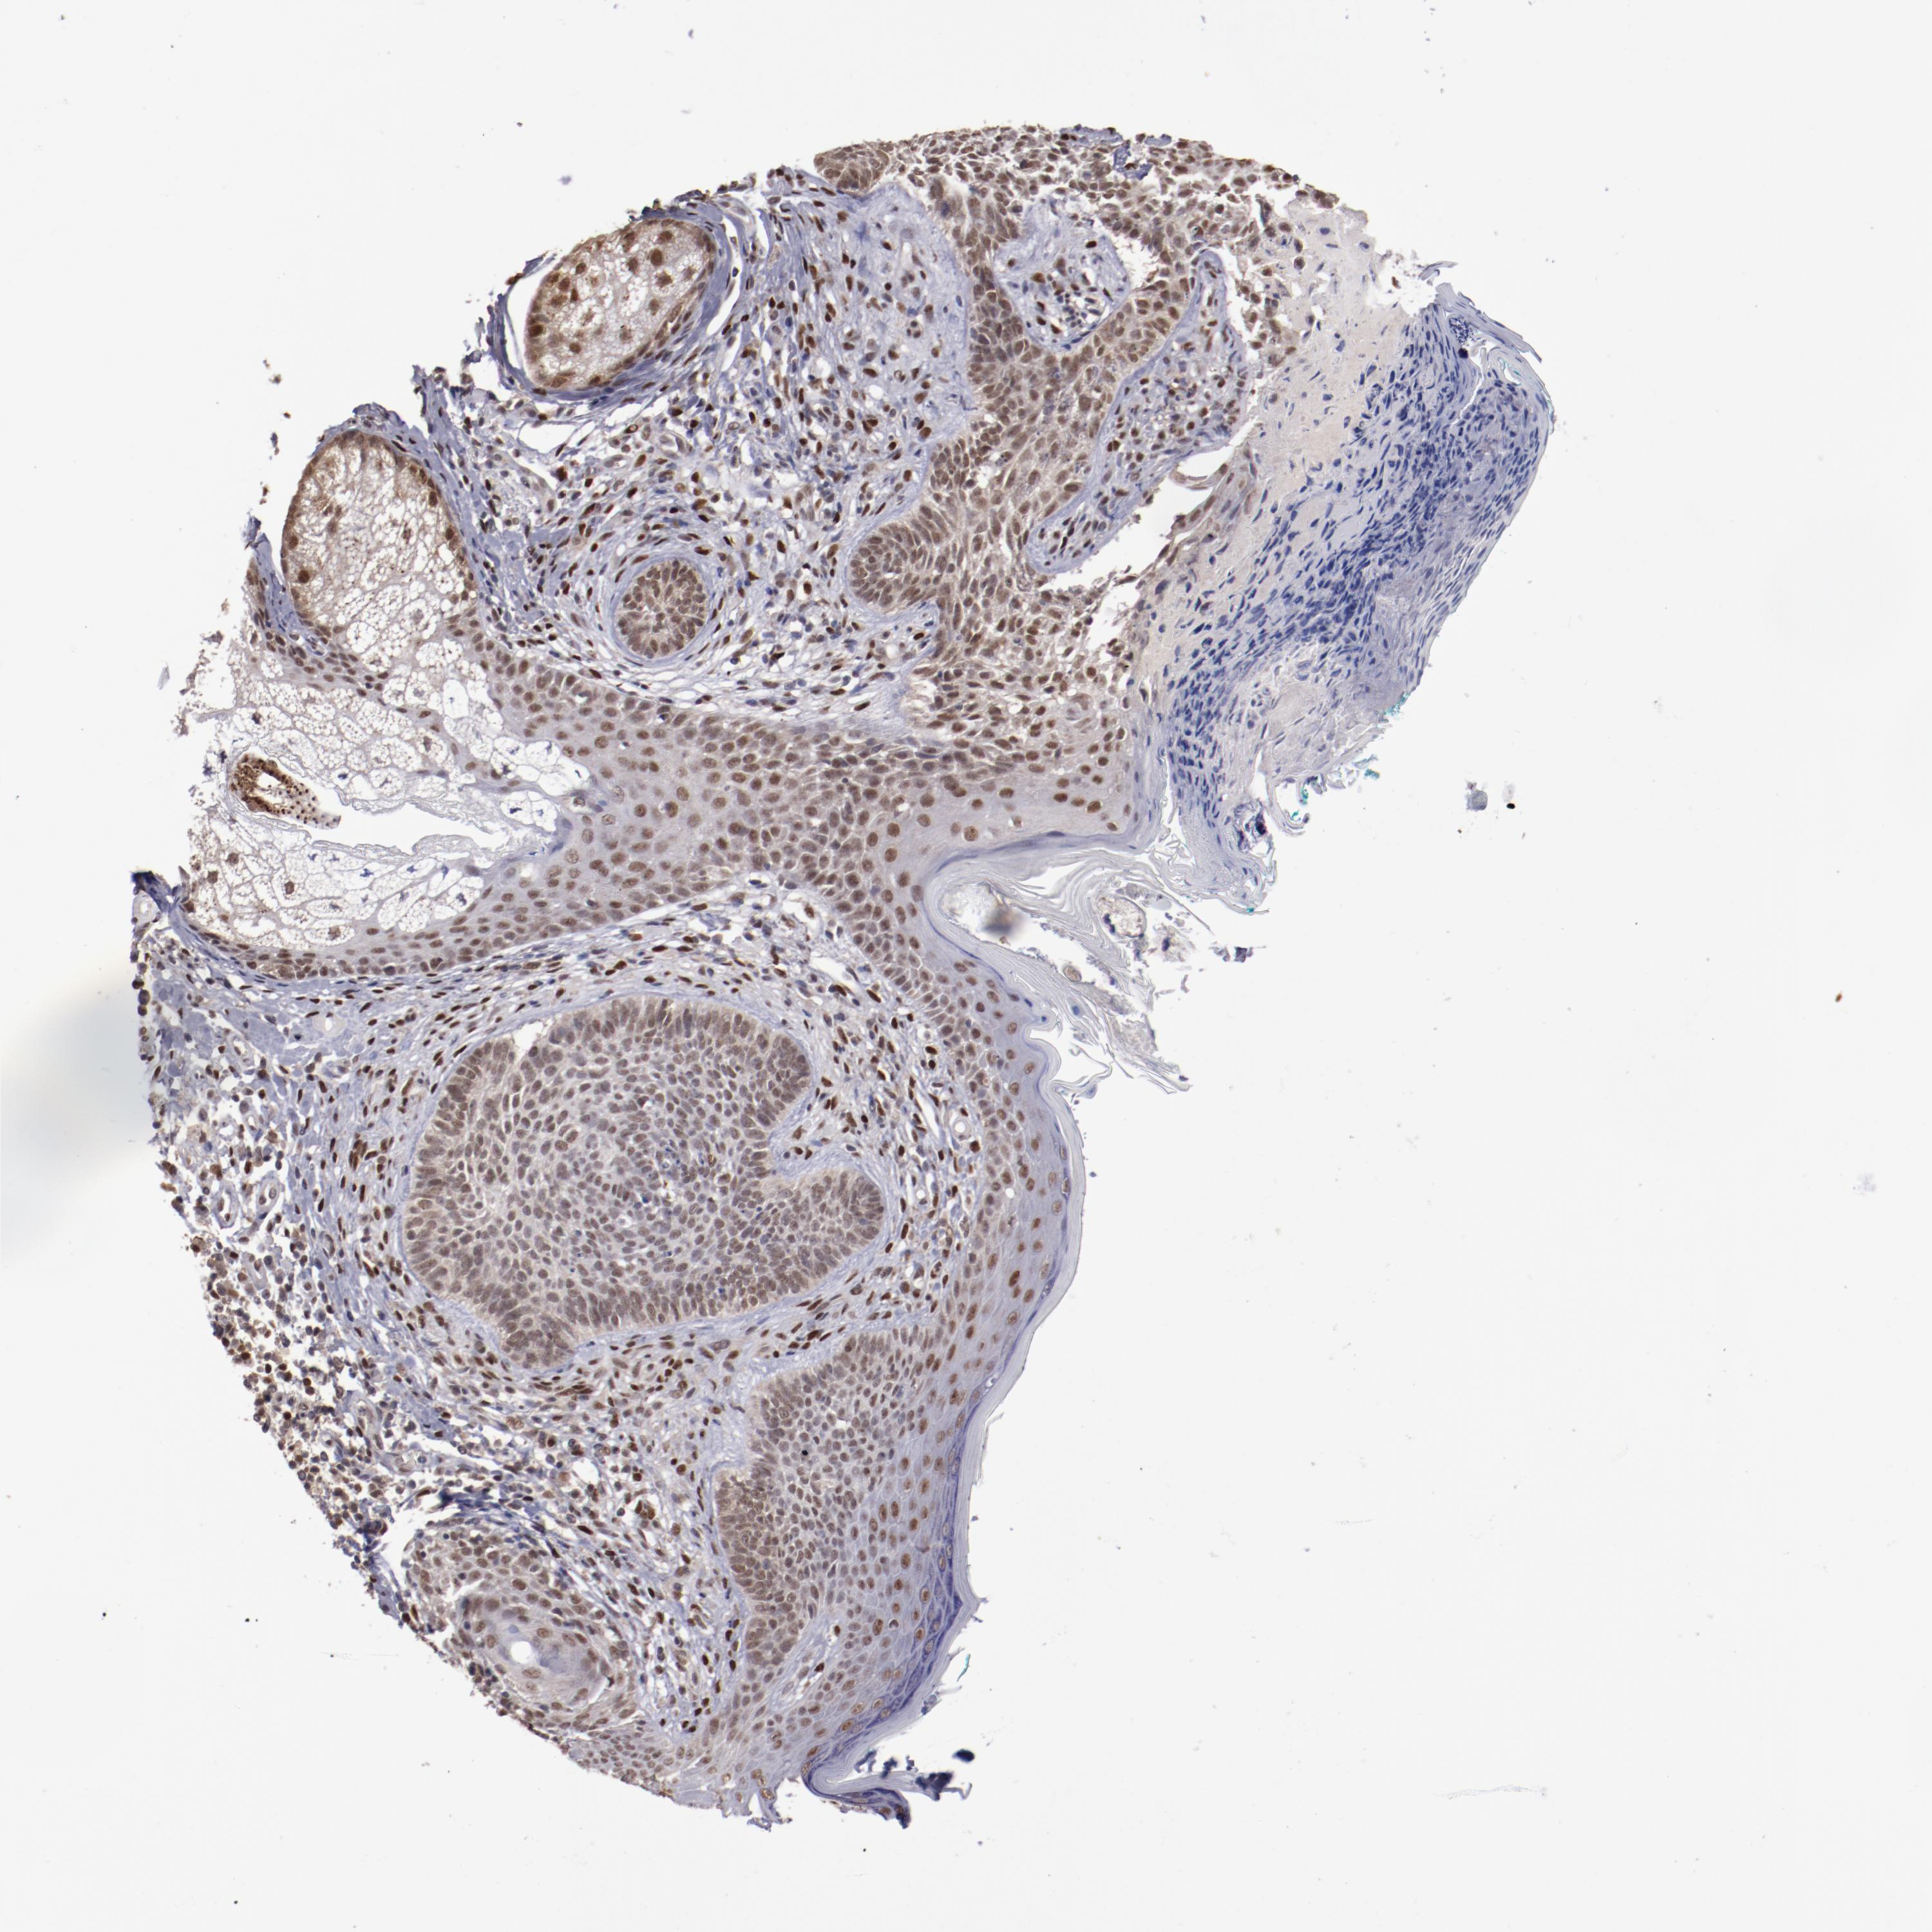

CANCER SKIN CANCER Show tissue menu

Basal cell and squamous cell cancer

SKIN CANCER - Protein expressioni

A mouse-over function shows sample information and annotation data. Click on an image to view it in a full screen mode. Samples can be filtered based on level of antibody staining by selecting one or several of the following categories: high, medium, low and not detected. The assay and annotation is described here.

Each image is clickable and will lead to virtual microscopy that enables deeper exploration of all samples and also displays staining intensity scores, fraction scores and subcellular localization as well as patient and tissue information for each sample.

Antibody CAB004318

Squamous cell carcinoma, NOS

Basal cell carcinoma